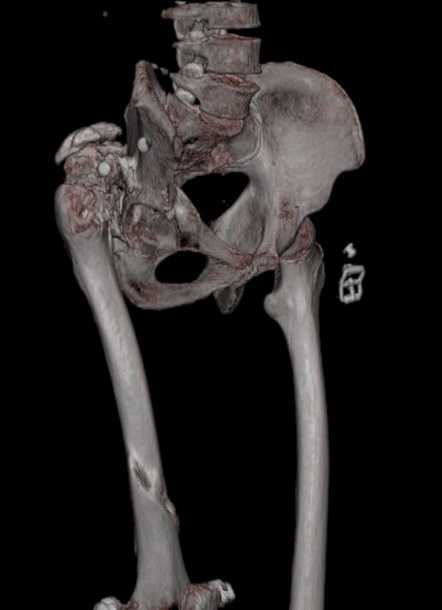

Уважаемые коллеги. Пациент 30 лет 3 года назад в результате травмы получил травматический дефект нижних конечностей до в/3 голеней, был пропущен вывих бедра.

В настоящее время очень неплохо ходит на протезах, движения в неоартрозе близки по объему к здоровой стороне. Основная жалоба - выраженная боль при ходьбе. планируем двухэтапное эндопротезирование - задним доступом мобилизовать проксимальный отдел бедра, резецировать шейку, аппаратом низвести бедро(головку оставить там где она есть, так как больших дефектов не видно(может пригодится в последующем?)). Вторым этапом бесцементное эндопротезирование. Насколько такой вариант реалистичен? Доступ для второго этапа? Может быть другие варианты?С уважением, Максим

Низводить надо обязательно, лучше в аппарате и лучше без остеотомии.

Если в аппарате низводиться не будет, то из небольшого доступа, лучше под контролем С-дуги выполнить остеотомию шейки. Без предварительного

низведения максимально возможная коррекция длины - 2,5-3 см.

Решение по ВВ придется принимать по месту.... Сумеете "подрыться" и получить хорошее покрытие чашки (+2 винта об-но) - хорошо, если нет -

костная аутопластика из головки.